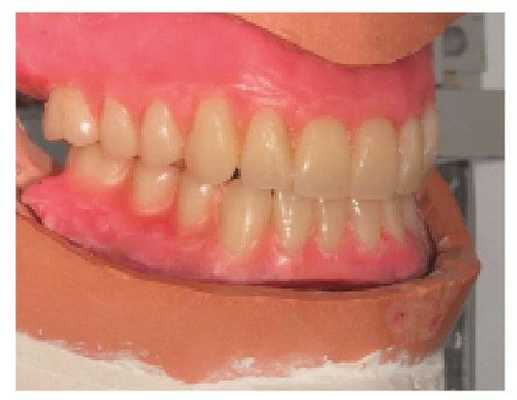

Реабилитация пациентов с полной адентией является непростой клинической задачей. Однако при реализации вышеописанного систематического подхода врачу удается добиться надлежащего восстановления функции, эстетики и фонетики в результате проведенного лечения (фото 12).

Фото 12. Вид окончательных конструкций полных съемных протезов в ротовой полости.

Данный подход также можно использовать при реабилитации пациентов съемными конструкциями на имплантатах, поскольку адаптивная способность таковых несколько ниже, чем обычных съемных протезов, учитывая стабильность установленных внутрикостных опор.